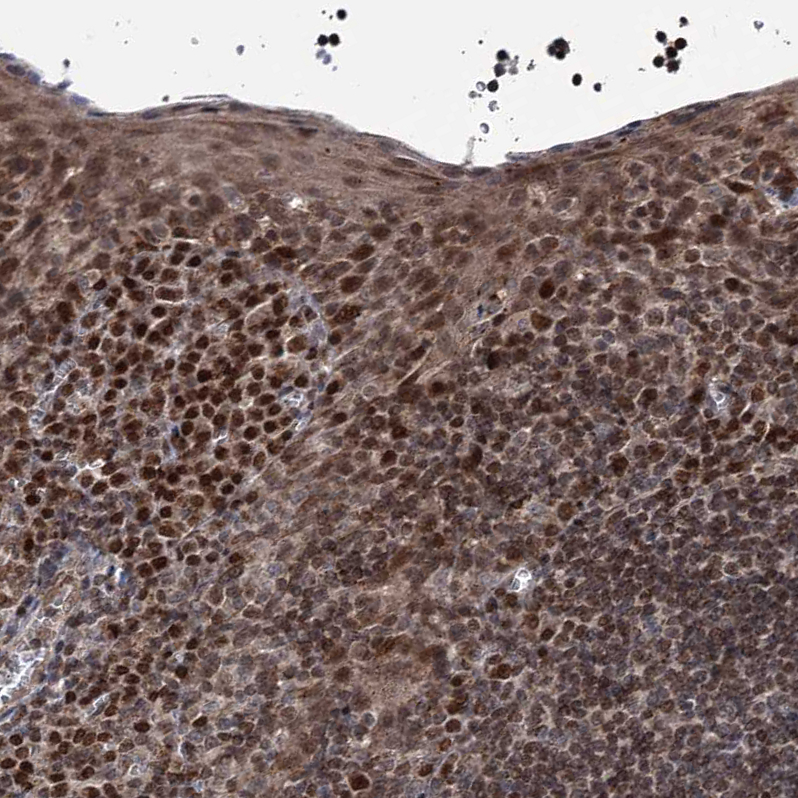

Immunohistochemical staining of human lymph node shows strong nuclear positivity in non-germinal center cells.